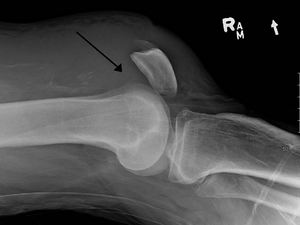

| An x-ray demonstrating quadriceps tendon rupture. Note the abnormal angle of the patella and soft-tissue swelling marked by the arrow. | |

A quadriceps tendon rupture is a tear of the tendon of the major leg extensor (rectus femoris), usually close to its insertion at the superior pole of the patella.